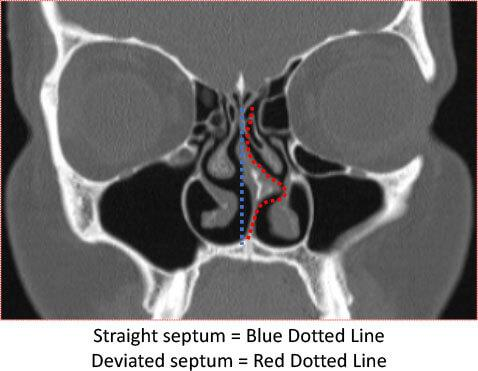

The nasal septum is the thin wall of cartilage and bone that divides your nose into two nostrils. In a perfectly aligned nose, air flows equally through both sides.

But in many people, this wall is crooked or shifted to one side—a condition known as a deviated septum.

- Imaging like CT scans in complex cases